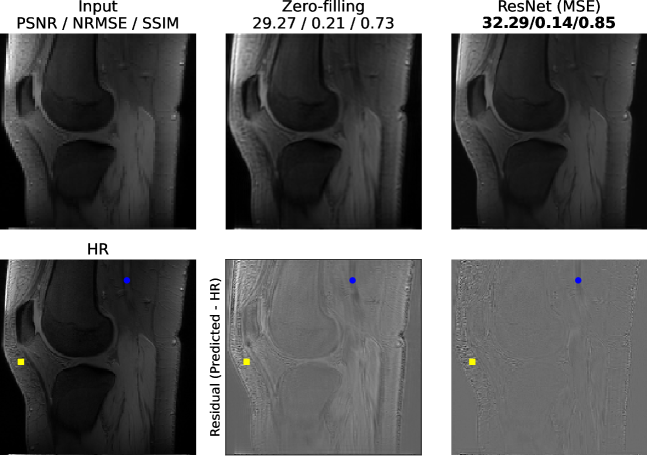

Figure 1 provides a qualitative comparison of the neural-network-based method (ResNet MSE loss) over the currently used method (k-space zero-filling) together with the LR input and the HR ground-truth (GT). It can be seen that the residual between the prediction and the GT is substantially improved by the network over the zero-filling approach. Regions the network is not able to recover typically have either very high frequencies such as subcutaneous fat anterior to the patella (yellow square) or strong blood flow such as the popliteal artery (blue dot). The regions of high interest for arthritis research, the tibiofemoral joint and patellofemoral joint, are resolved with high accuracy by the network.